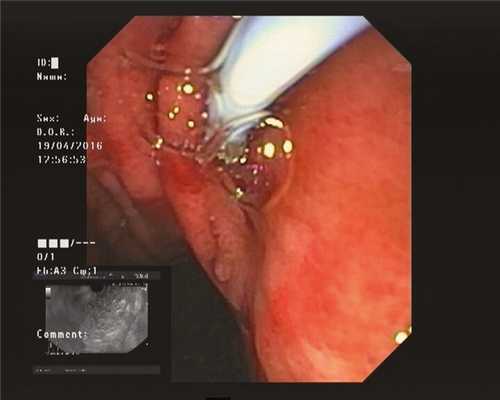

5. Установка трехлепесткового стента MTW таким образом, чтобы конец, содержащий два лепестка, оставался в просвете кисты (рис. 3, 4). Рис. 4. Эндоскопическая цистогастростомия с установкой в кисту трехлепесткового стента MTWE. Рис. 3. Эндоультразвуковое сканирование псевдокисты поджелудочной железы после цистотомии (в просвете определяется катетер) (пациент 1).